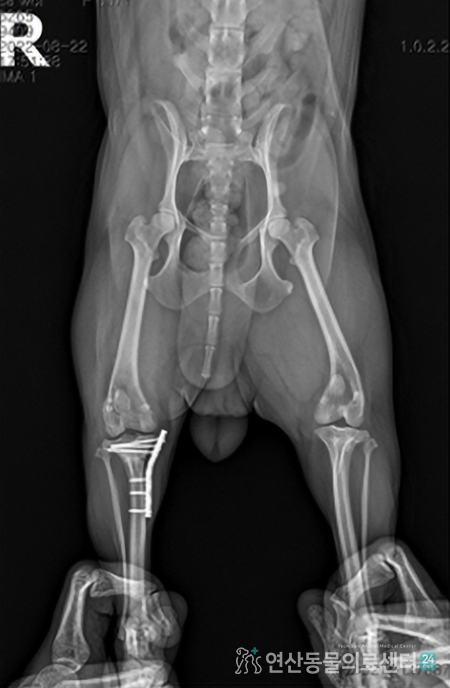

MPL, TPLO 슬개골 탈구 + 십자인대슬개골 탈구 수술과 십자인대 수술

동시 진행 케이스